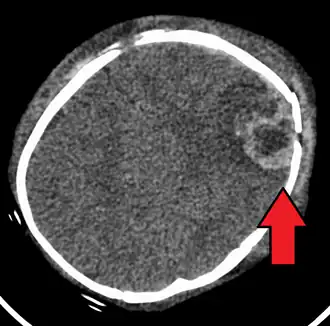

Vooral het hoofd van een baby is erg broos en kwetsbaar omdat het naar lichaamsverhouding erg groot is en de nekspieren van het jonge kind nog maar weinig zijn ontwikkeld. Wanneer de baby zodanig wordt geschud dat het hoofdje heen en weer beweegt, kan het schudden beschadigingen van hersenen, bloedvaten en zenuwen veroorzaken, met blijvend letsel of met de dood tot gevolg. De gevolgen van de beschadiging aan bloedvaten, de hersenen of hersenzenuwen bij het shakenbabysyndroom zijn blijvend. Ieder jong kind dat, heftig of niet, op deze wijze wordt geschud, gedurende vijf seconden of langer, heeft onmiddellijk medische hulp nodig. Snelle medische hulpverlening kan het verergeren van de gevolgen voorkomen, bijvoorbeeld door een hersenoedeem te behandelen.

Er zijn de volgende medische indicaties voor het shakenbabysyndroom:

- Hersenbloeding

- Hersenoedeem

- Hersenkneuzing